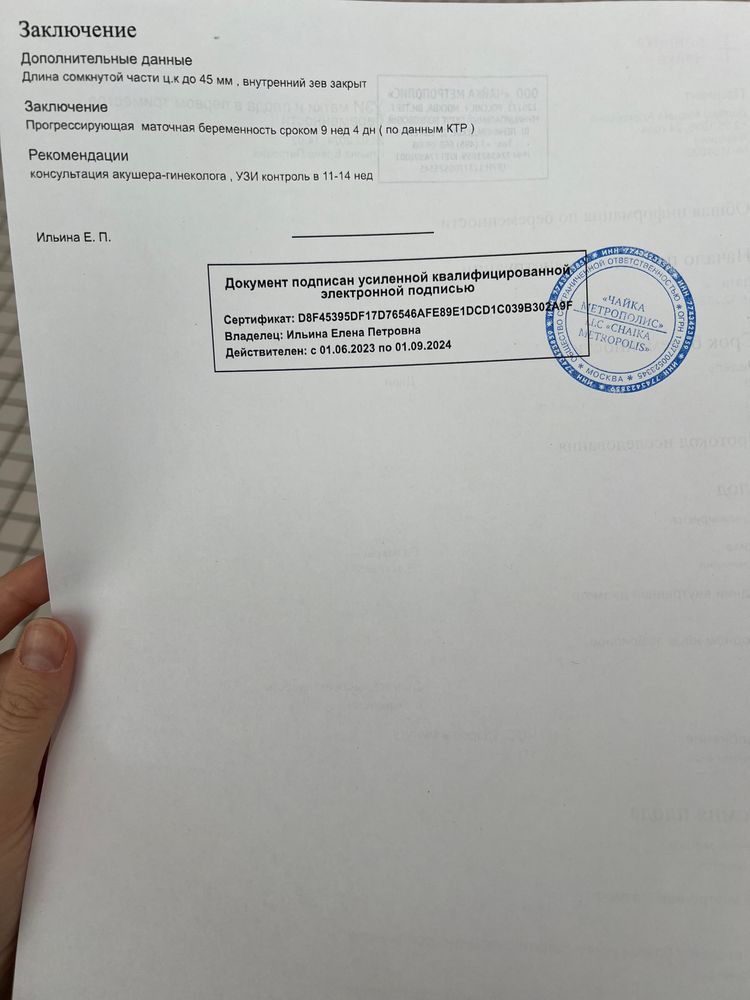

Здравствуйте! Дорогие дамы, прикрепляю 2 узи от 13.02.2024 и от 24.02.2024. Нормально малыш вырос? Узистка странно написала на первом узи, что малыш по ктр на 8 недель и 3 дня, хотя аппарат показывал 8 недель ровно. Сегодня у меня (24.02.2024) 10 недель ровно, а аппарат показал 9 недель и 4 дня. На самом первом узи в 6 недель и 3 дня мне аппарат показывал, что малыш по размерам на 6 недель ровно. То есть, везде стабильно 3 дня разница с акушерским сроком. Сегодня аппарат показал ЧСС 177, но узистка написала в протоколе 171, почему-то.